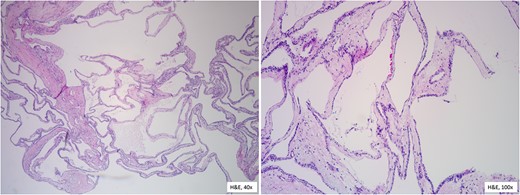

Two weeks later, the patient presented for pylorus-preserving pancreaticoduodenectomy and peri-portal lymph node dissection. Intraoperatively, the entire pancreas and surrounding structures were distorted. The tumor was closely adhered to the SMV and portal vein. Despite tedious dissection, the SMV had to be repaired with 4–0 Prolene sutures. There was no evidence of other organ or lymph node involvement. The estimated blood loss was 800 cc and patient received blood products during the case. The patient’s postoperative course was uneventful. She was followed in the intensive care unit until postoperative Day 3 and discharged on postoperative Day 8 without any complications. The final pathology report confirmed the diagnosis of benign serous microcystic adenoma measuring 15 cm in diameter with no tumor invasion into the interstitium or vessels. Analysis of the specimen revealed acute bile duct inflammation with mucosal ulceration, chronic pancreatitis, acute and chronic cholecystitis, and subacute and chronic ampullary wall inflammation. Microscopic examination (Fig. 5) of the specimen shows glycogen-rich cysts lined by a single layer of cuboidal or flattened cells. Sectioning through the mass revealed tan-yellow to pink, multicystic cut surface containing thin, brown fluid.

Histopathological features reveal the cysts lined by a single layer of cuboidal cells with clear, glycogen-rich cytoplasm, without atypia.